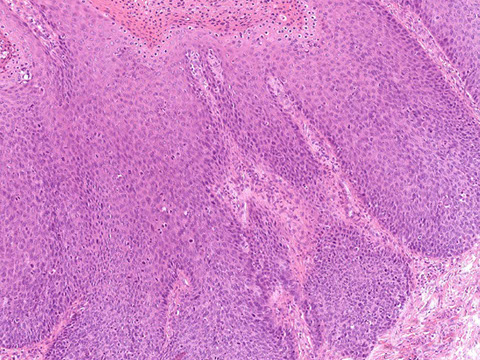

Microscopic pathology of Crohn disease. A, Haphazard crypt organization results from repeated injury and regeneration. B, Noncasearing granuloma. C, Transmural Crohn disease with submucosal and serosal granulomas (arrows)

Microscopically, Crohn disease is characterized by transmural inflammation. Here, inflammatory cells (the bluish infiltrates) extend from mucosa through submucosa and muscularis and appear as nodular infiltrates on the serosal surface adjacent to fat. Note the granulomatous inflammation.